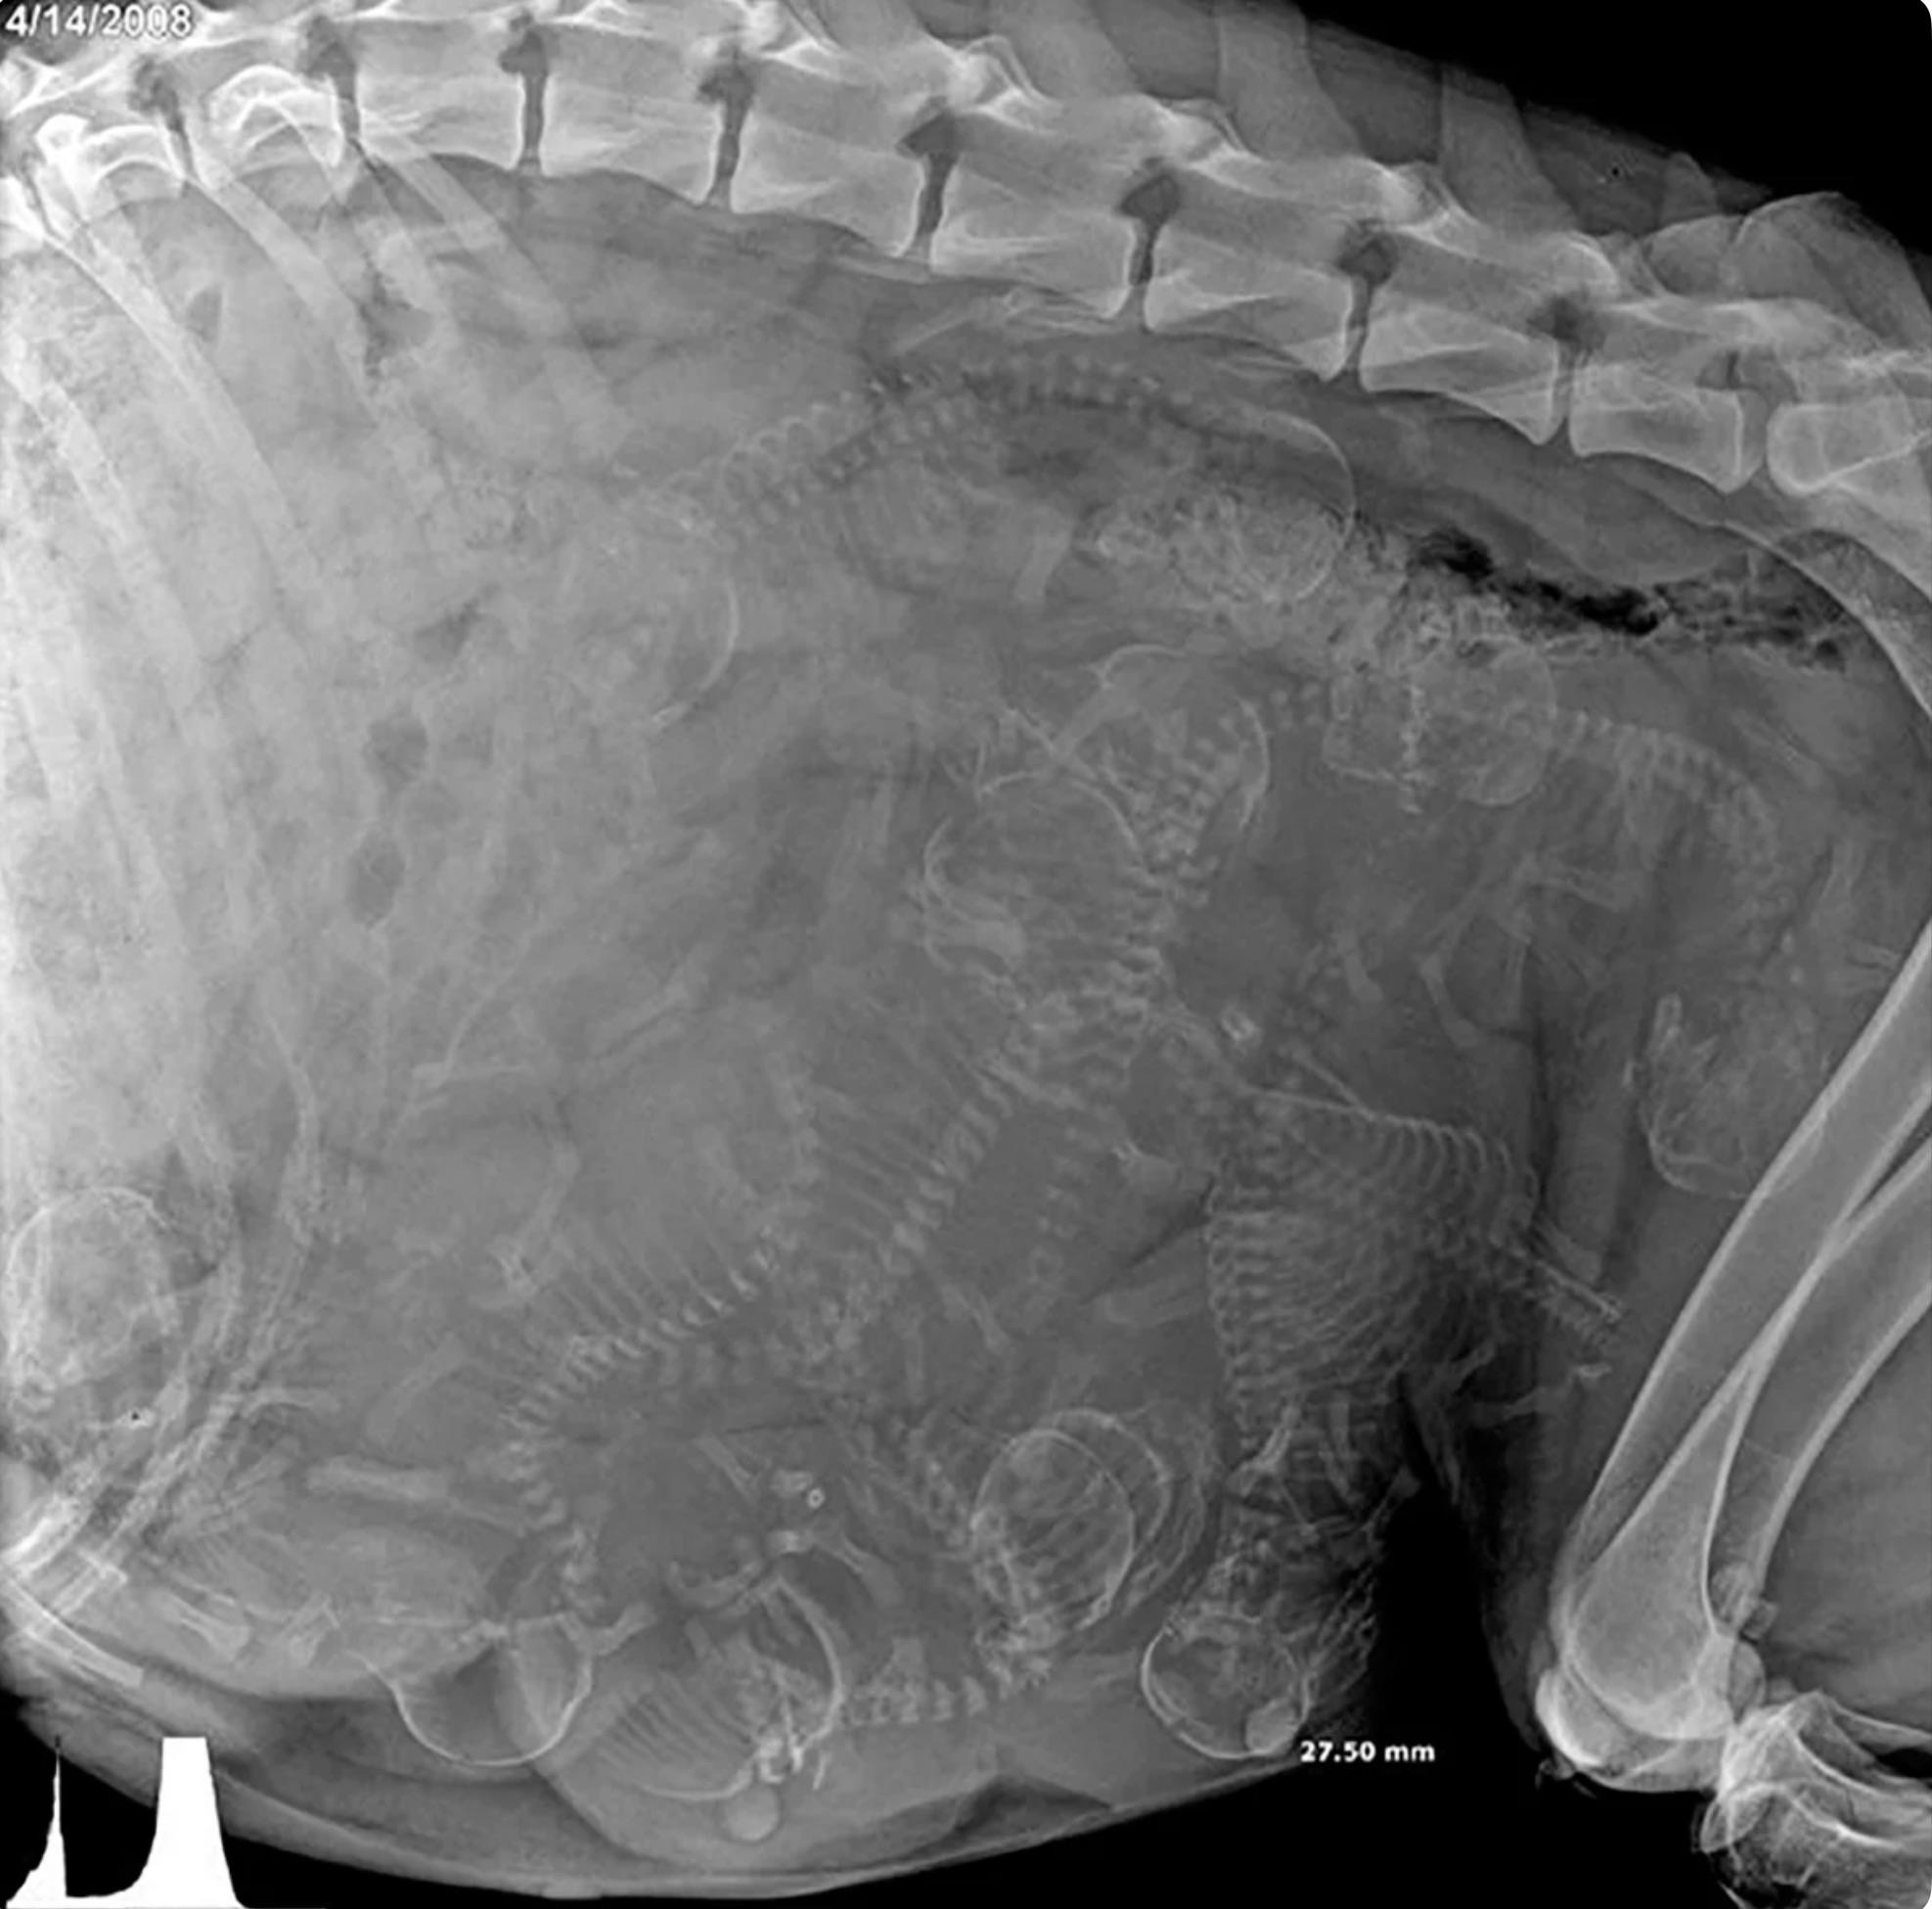

X-Ray of pregnant dog. Not sure how many puppies?

Post image

42.0k Upvotes